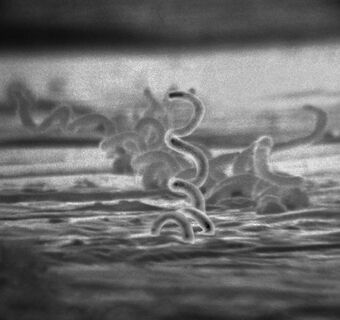

Treponema pallidum.jpg

Electron micrograph of Treponema pallidum